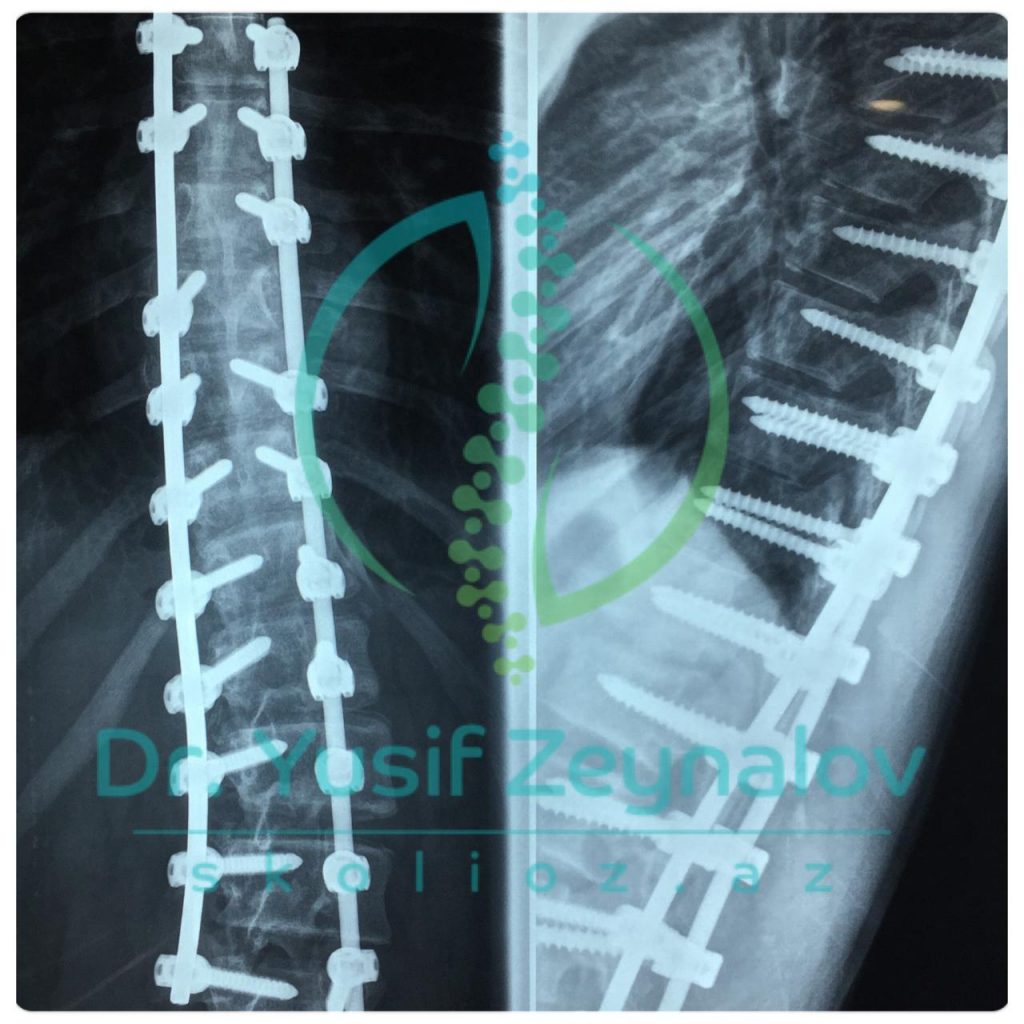

İDİOPATİK SKOLİOZ. LUMBAR DEFORMASİYA. COBB BUCAĞI 65°